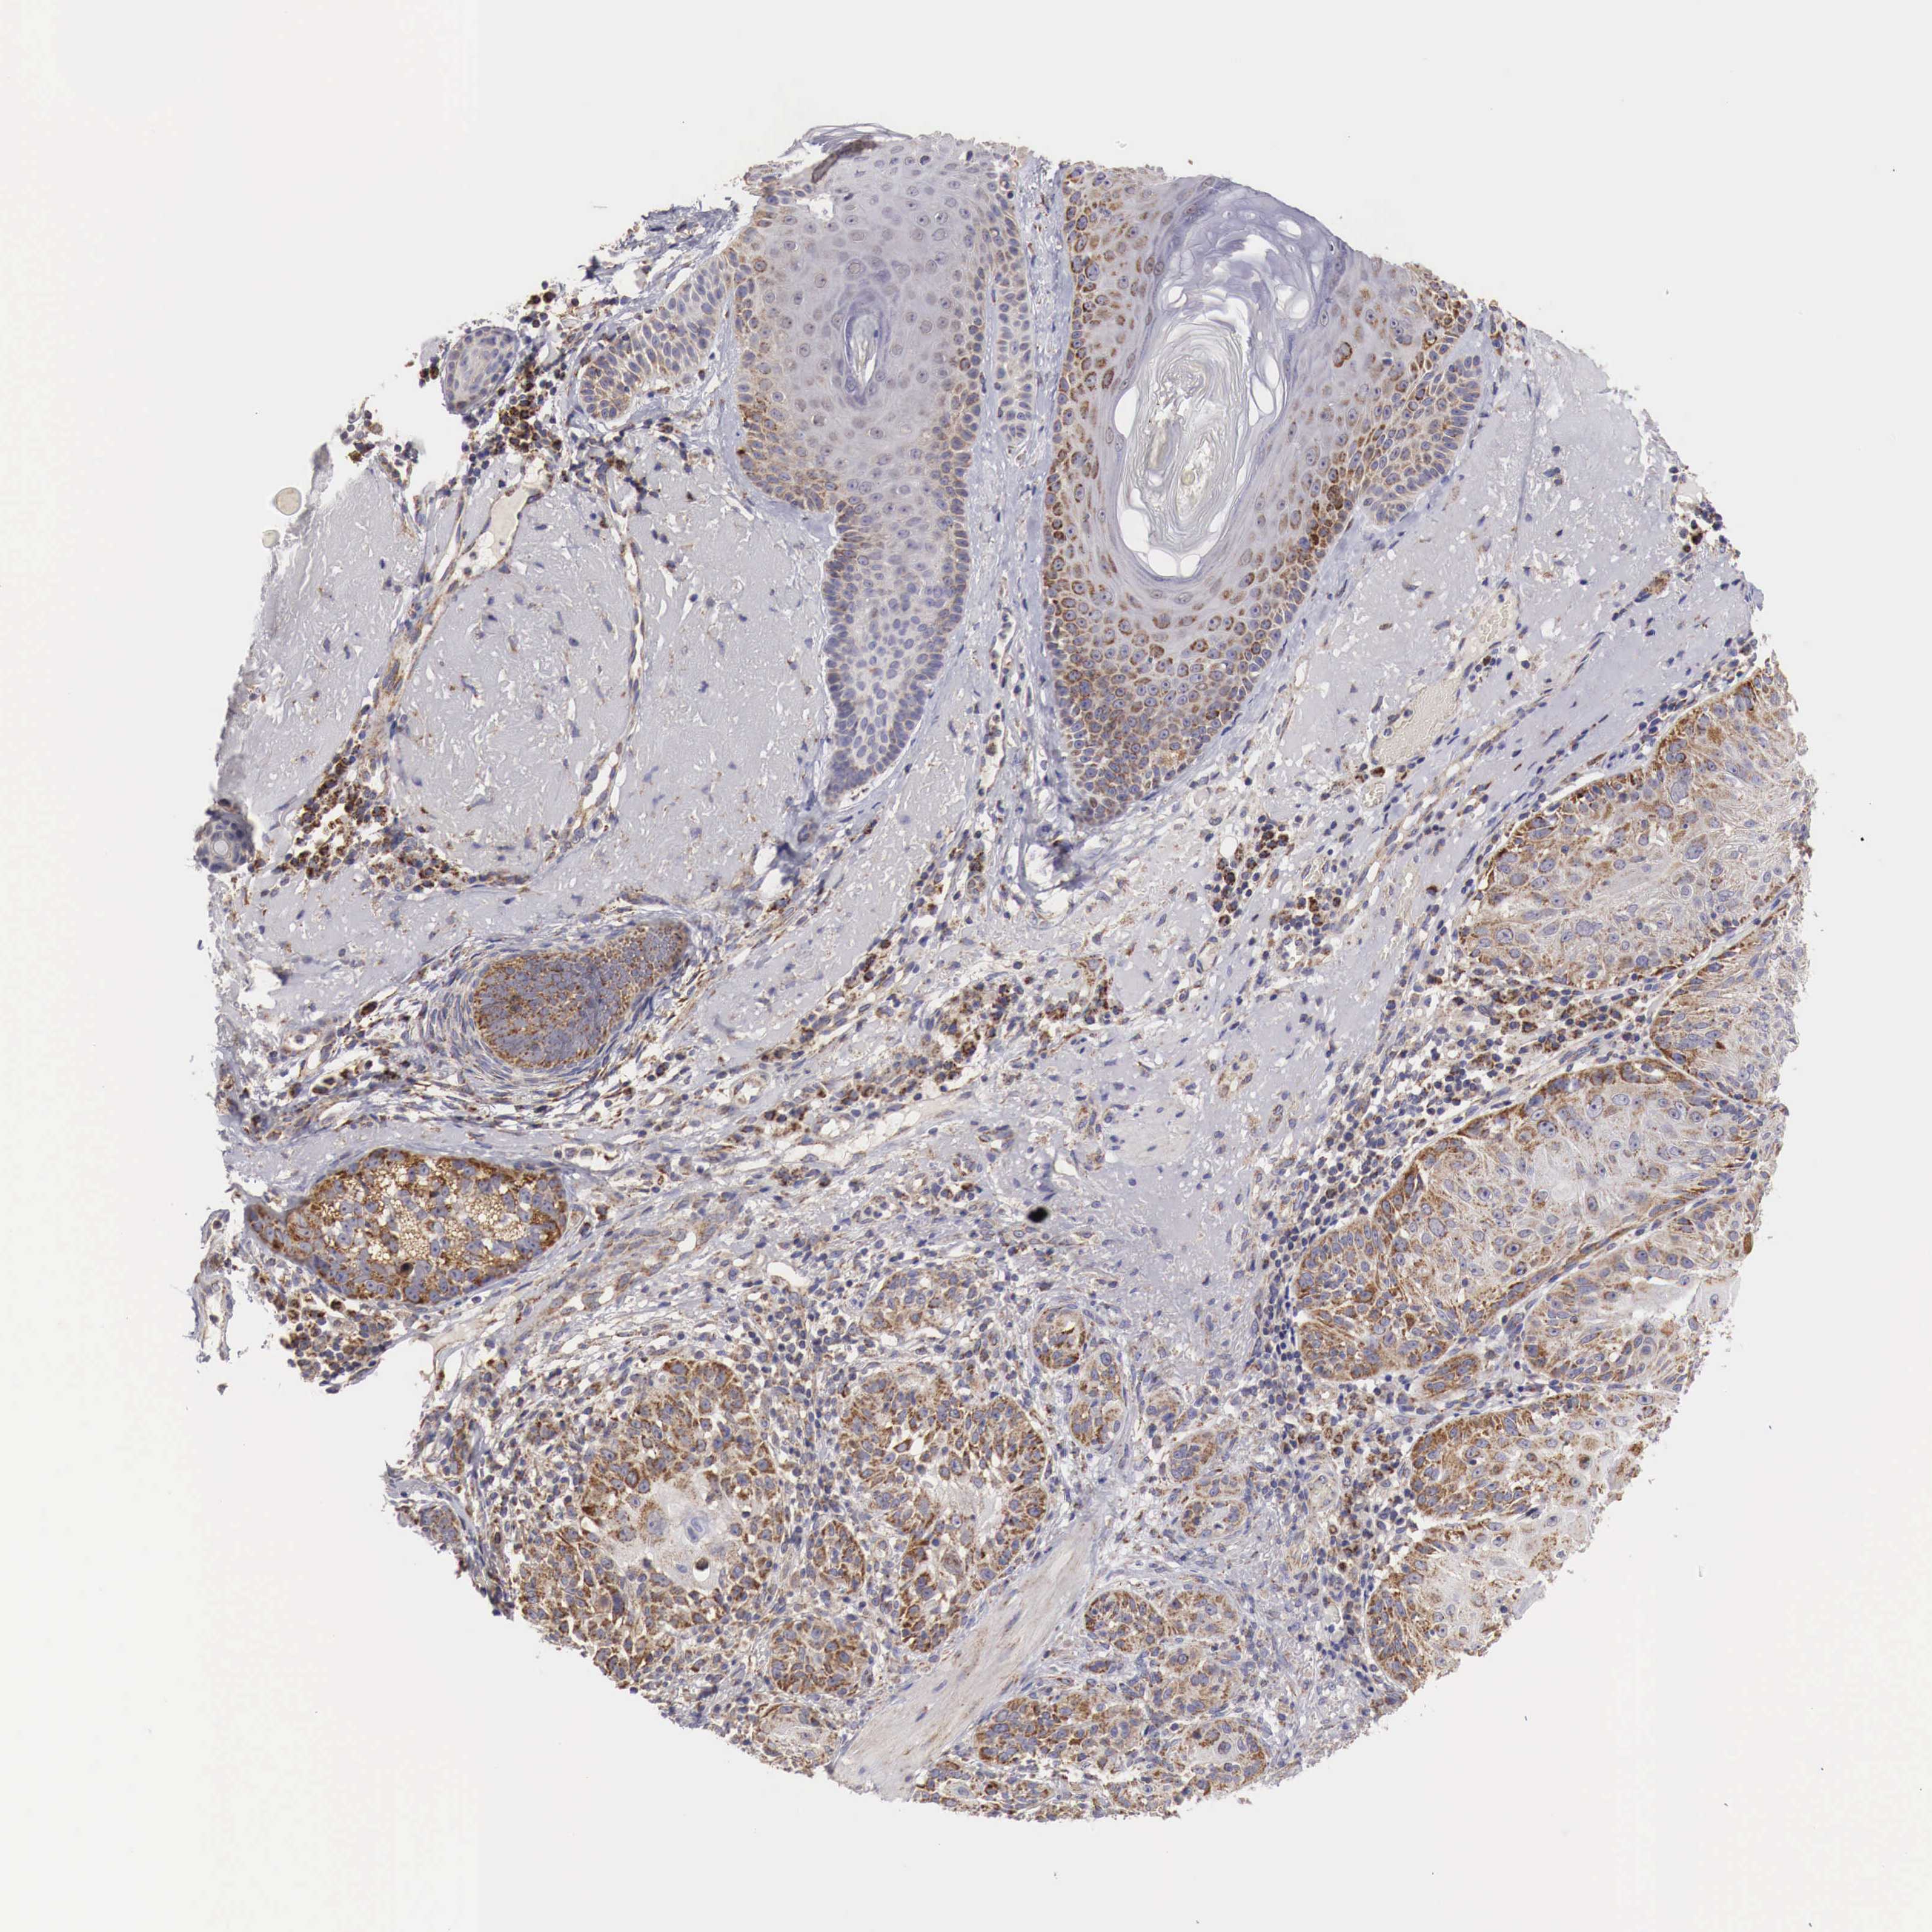

SKIN CANCER - Protein expressioni

A mouse-over function shows sample information and annotation data. Click on an image to view it in a full screen mode. Samples can be filtered based on level of antibody staining by selecting one or several of the following categories: high, medium, low and not detected. The assay and annotation is described here.

Each image is clickable and will lead to virtual microscopy that enables deeper exploration of all samples and also displays staining intensity scores, fraction scores and subcellular localization as well as patient and tissue information for each sample.

Antibody HPA000527

Staining

High

Intensity

Strong

>75%

Location

Nuclear

Squamous cell carcinoma, NOS

Basal cell carcinoma